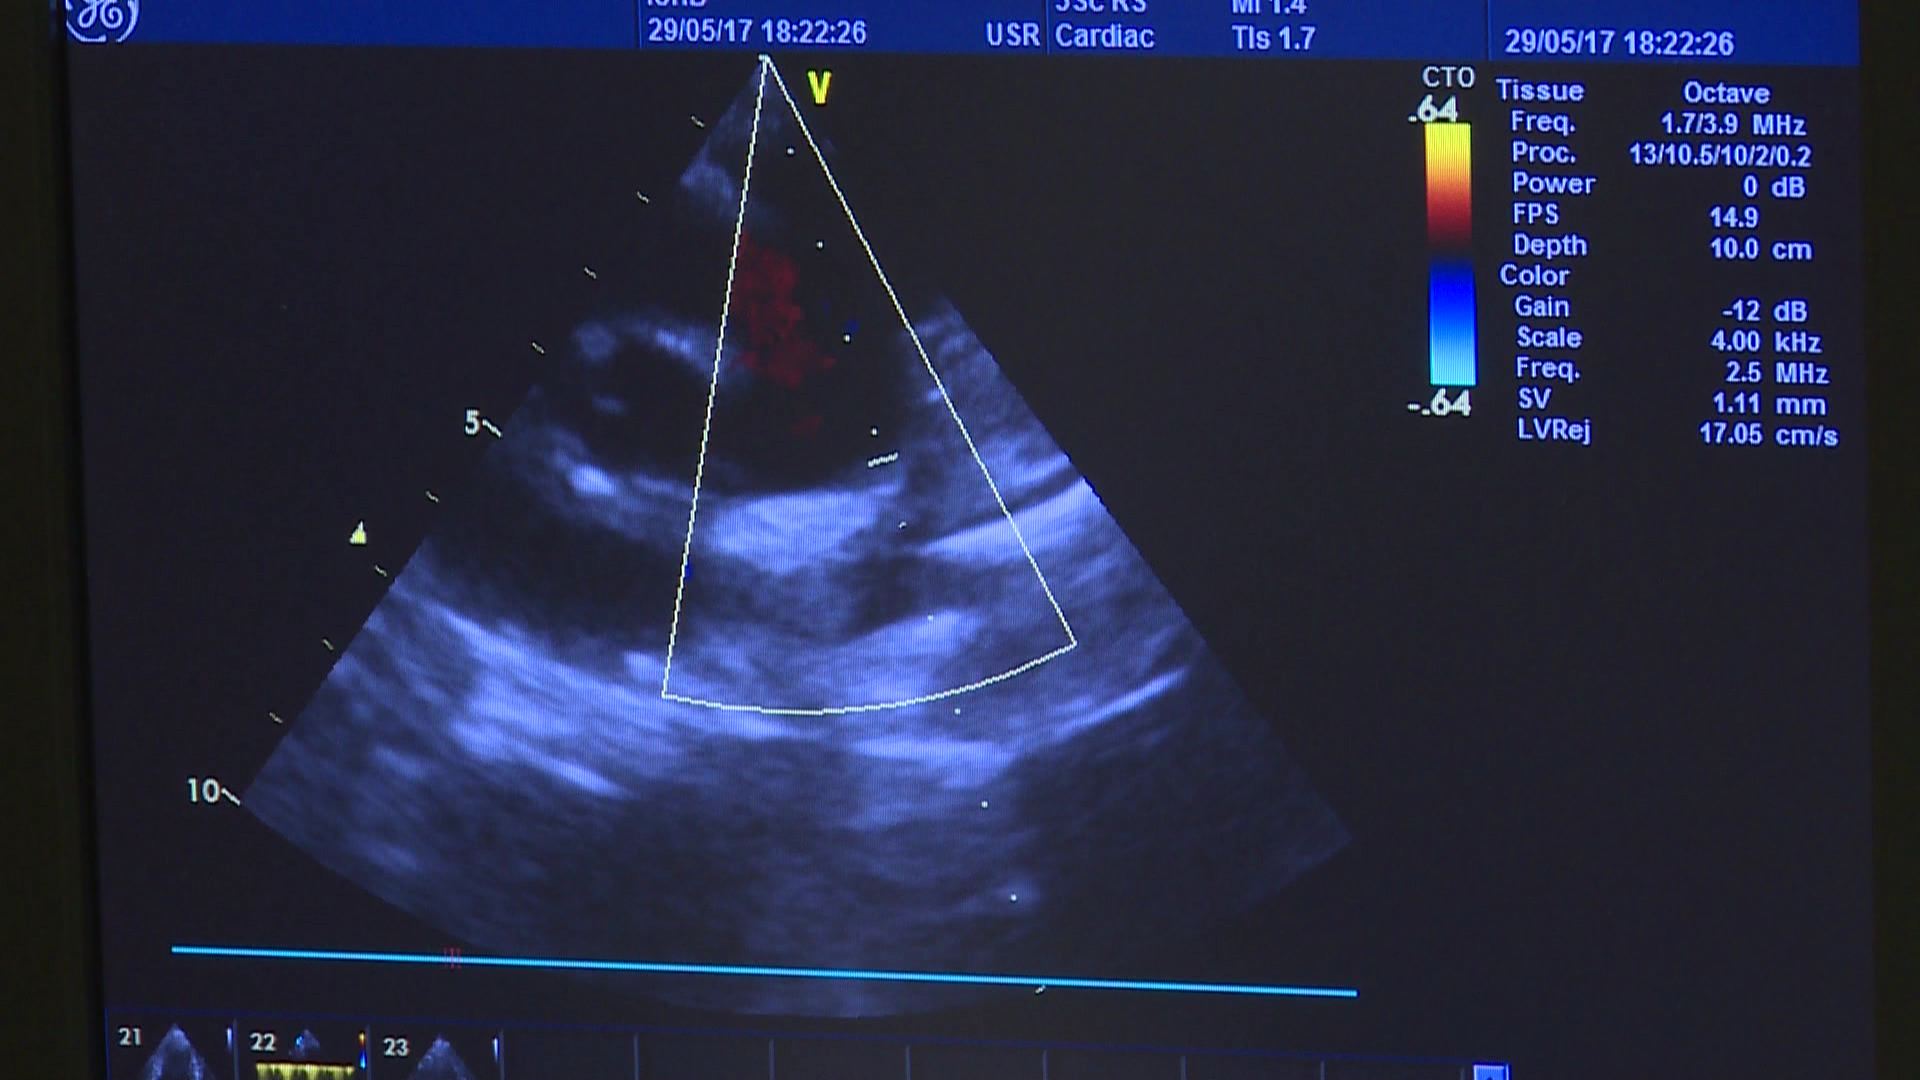

ახალშობილთა გულის თანდაყოლილი მანკების კრიტიკული ფორმების გამოსავლენად აჭარის ჯანდაცვის სამინისტრო ახალი პროექტის განხორციელებას იწყებს. ამბობენ, რომ პროექტის მიზანი გულის თანდაყოლილი...